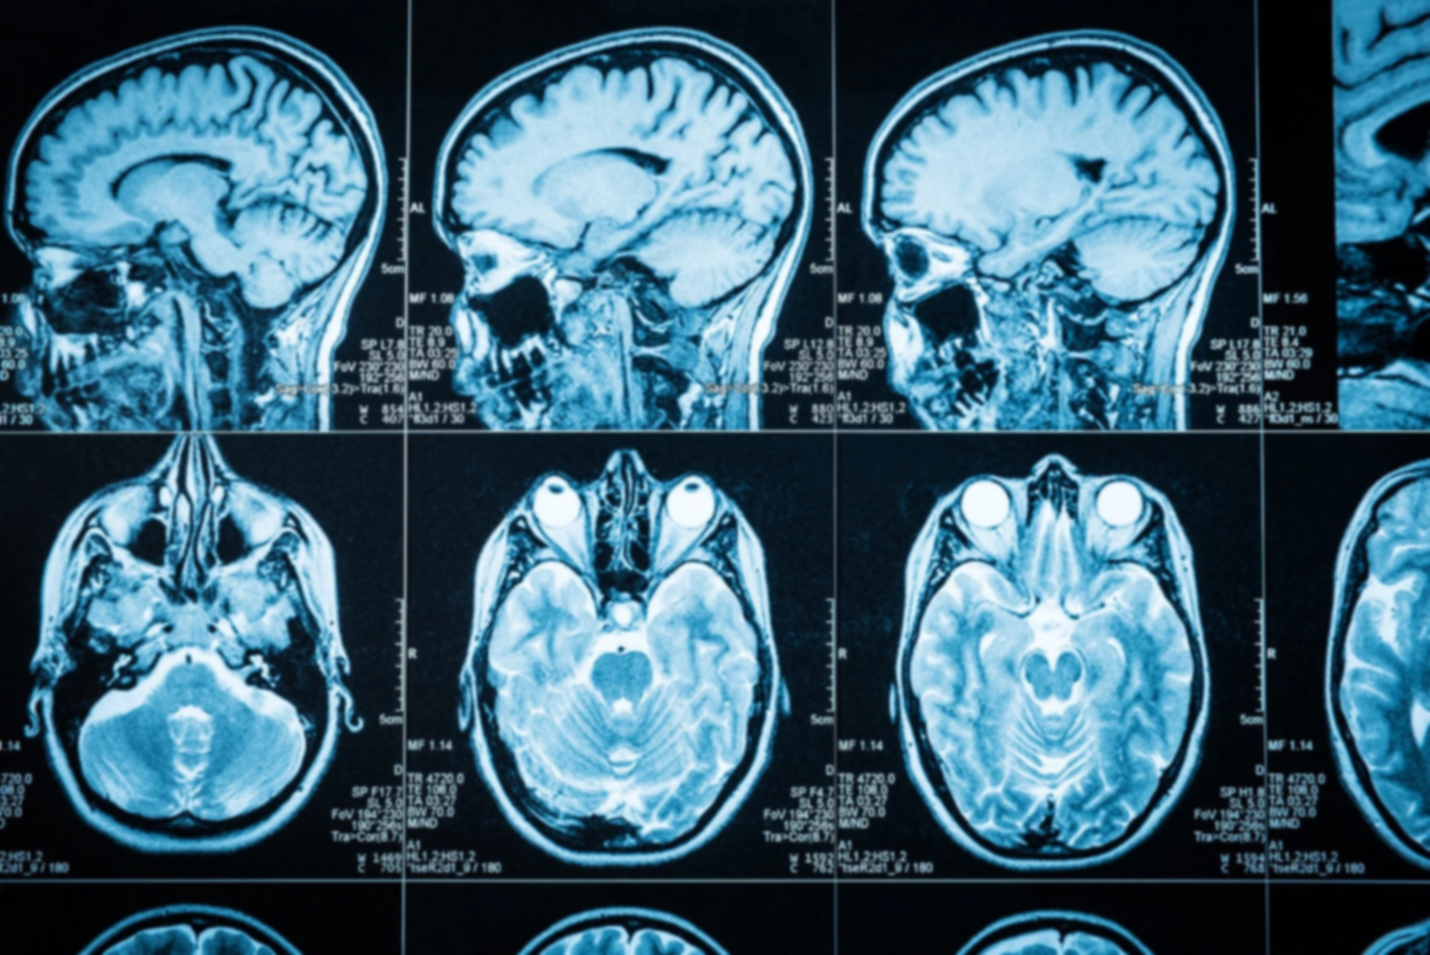

Il ne cesse de travailler, de réguler, d’améliorer et d’agir : il s’agit véritablement d’une machine infernale impliquée dans la quasi-totalité des réactions de notre corps – qu’elles soient physiologiques ou néfastes. Un kyste épidermique au niveau du cerveau est par excellence un processus néfaste survenu lors du développement embryonnaire.

Cependant, le cerveau ne capitule pas si facilement sinon les seuls êtres humains à exister auraient été Adam et Eve. De ce fait, ces cellules peuvent rester piégées toute une vie sans causer le moindre problème. Dans d’autres cas, dû à leurs capacités sécrétoires au sein du cerveau, elles peuvent être à l’origine de l’accumulation de kératine le plus souvent près du cervelet et du tronc cérébral. De ce fait, le cerveau se retrouve compresser ce qui va causer une perturbation des fonctions neurologiques cruciales et des symptômes communs entre les patients atteints ; notamment des maux de tête, des nausées ou encore des troubles d’équilibre.